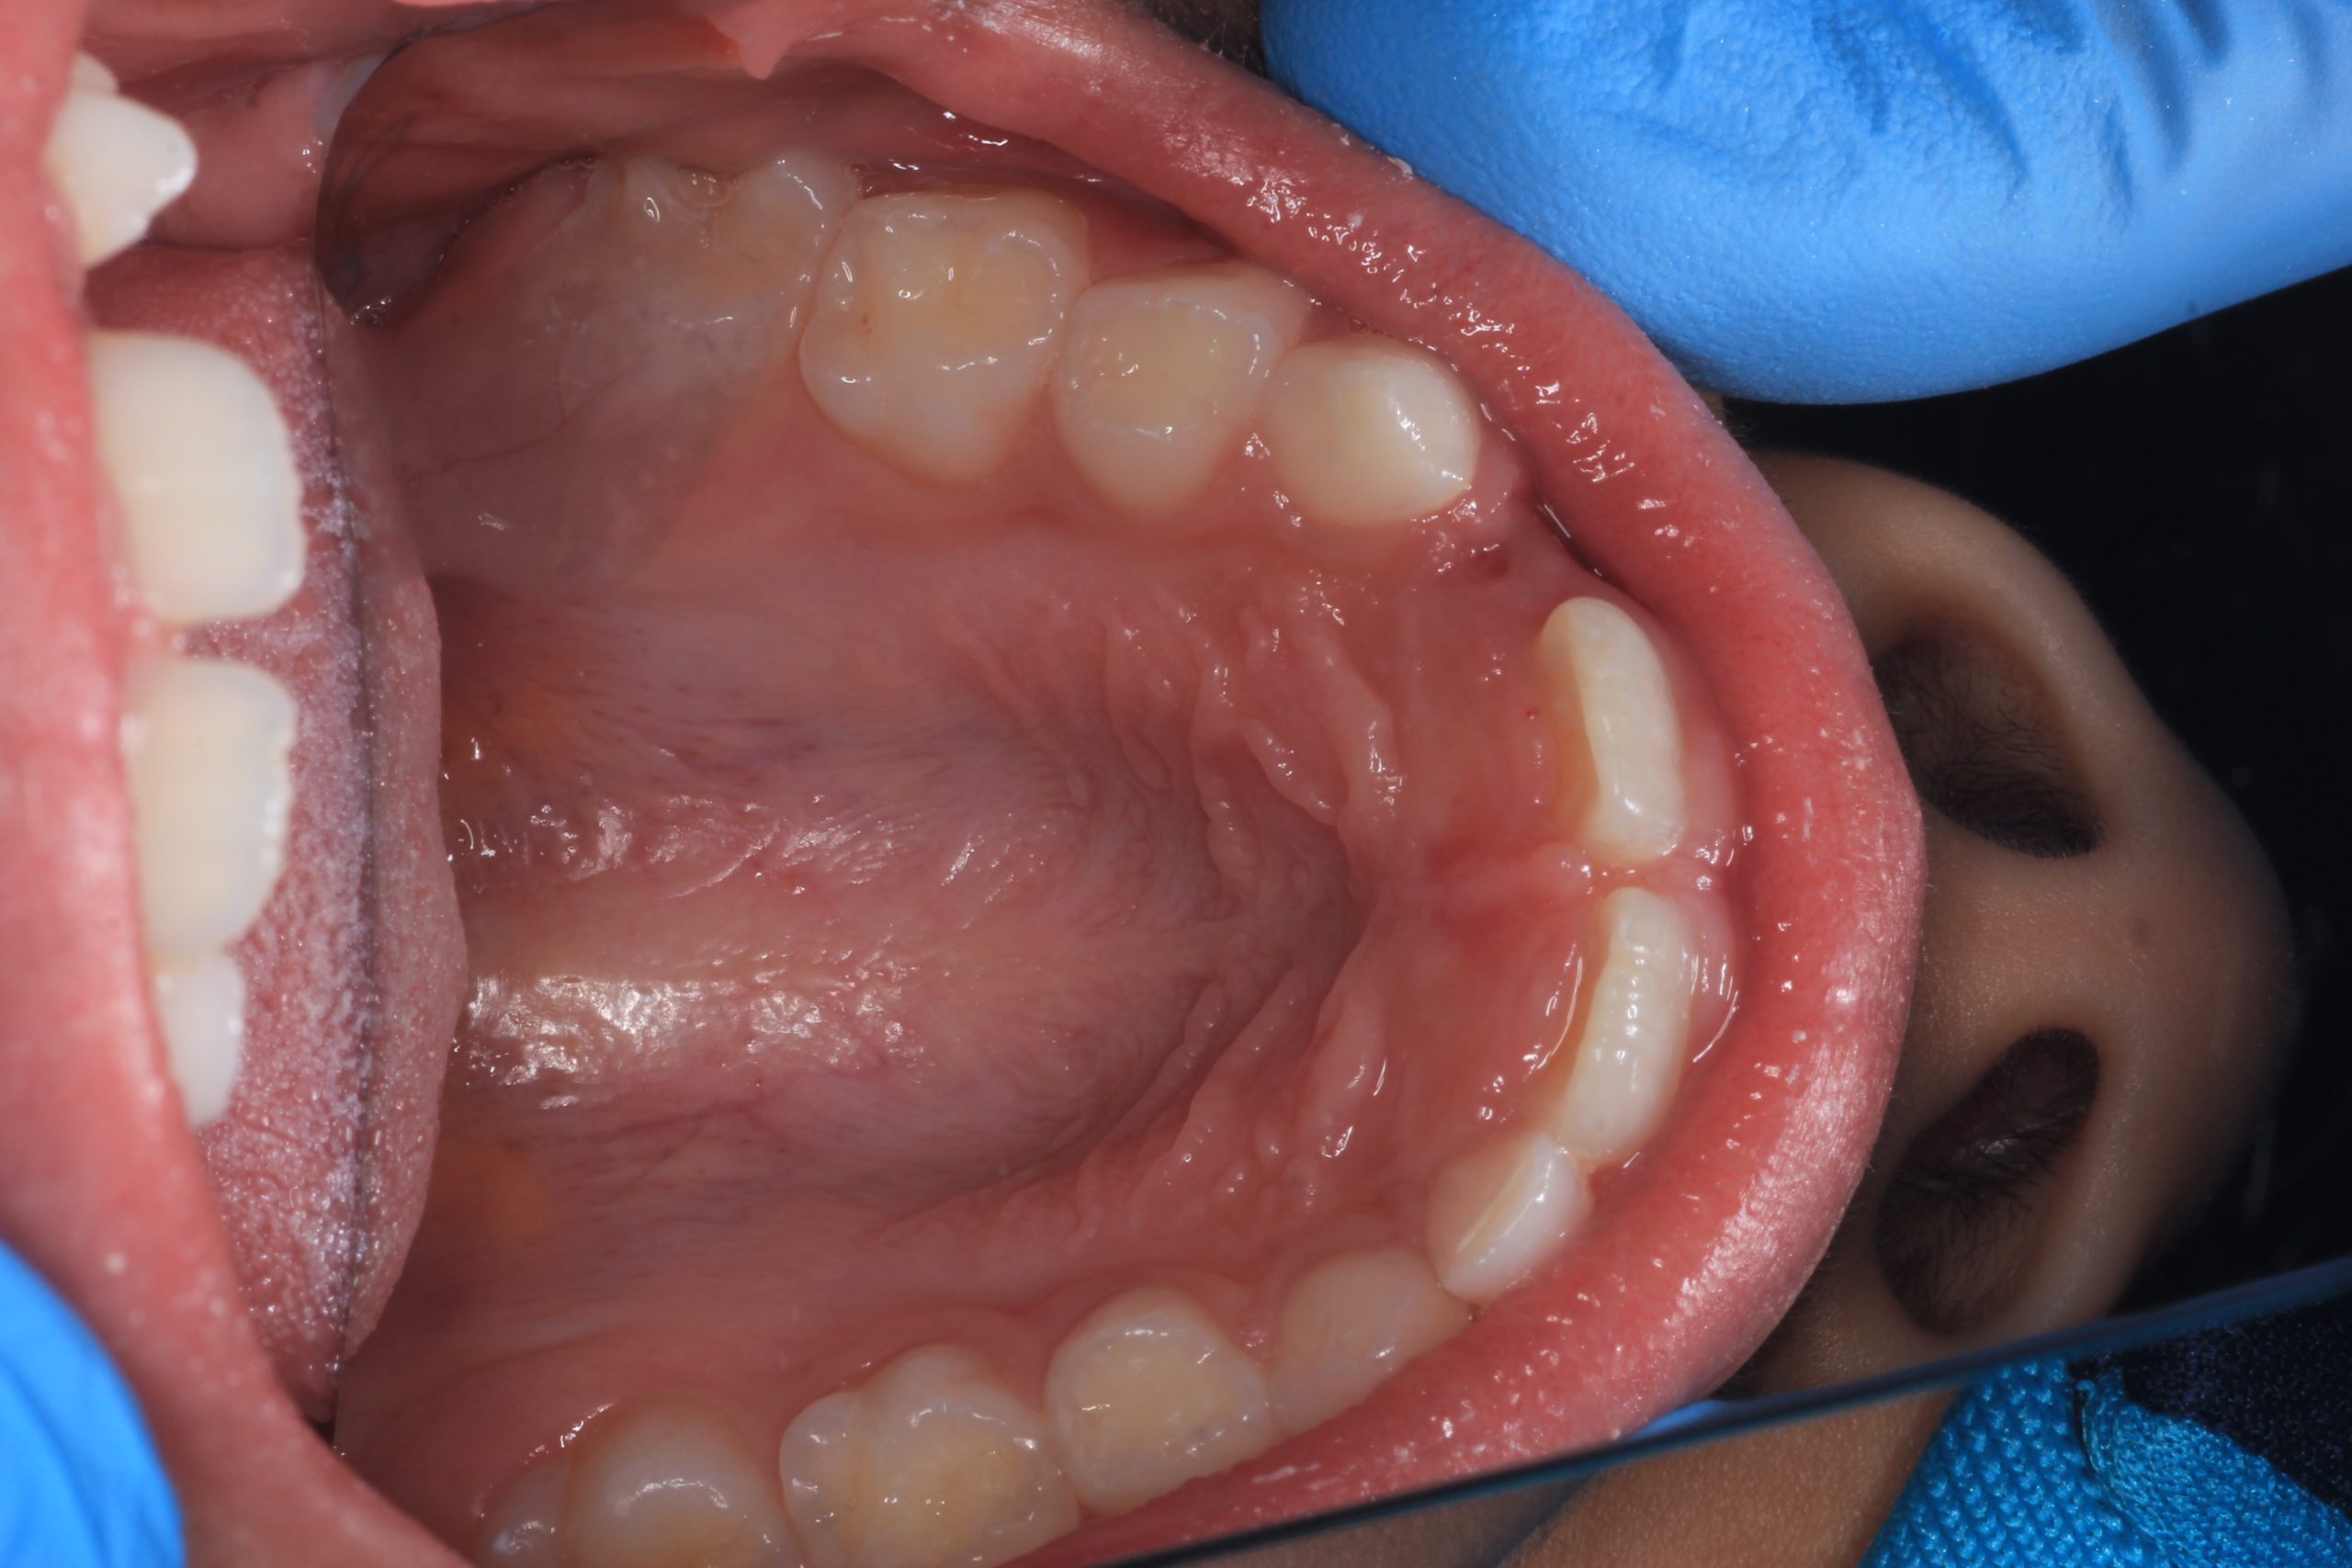

We examine the condition of teeth, gums, and bite. - Plaque Disclosure with Special Indicators

Areas that weren’t cleaned well appear purple. The darker the shade, the older the plaque. This helps both kids and parents understand where brushing needs to improve. - Brushing Training & Home Care Tools Selection